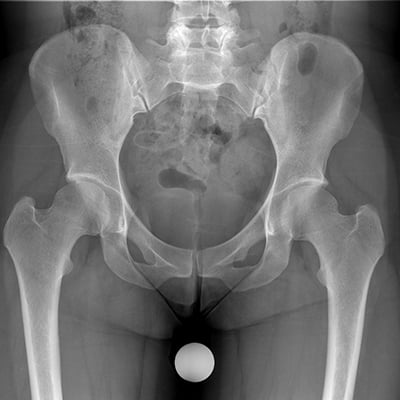

This module will help you achieve optimal images when performing pelvis, hip, cross-table hip, sacrum and coccyx, and SI joint examinations. Patient preparation and positioning are discussed, as well as technical settings and patient instructions. Descriptions and images of the expected anatomical structures are included, as well as image evaluation criteria.